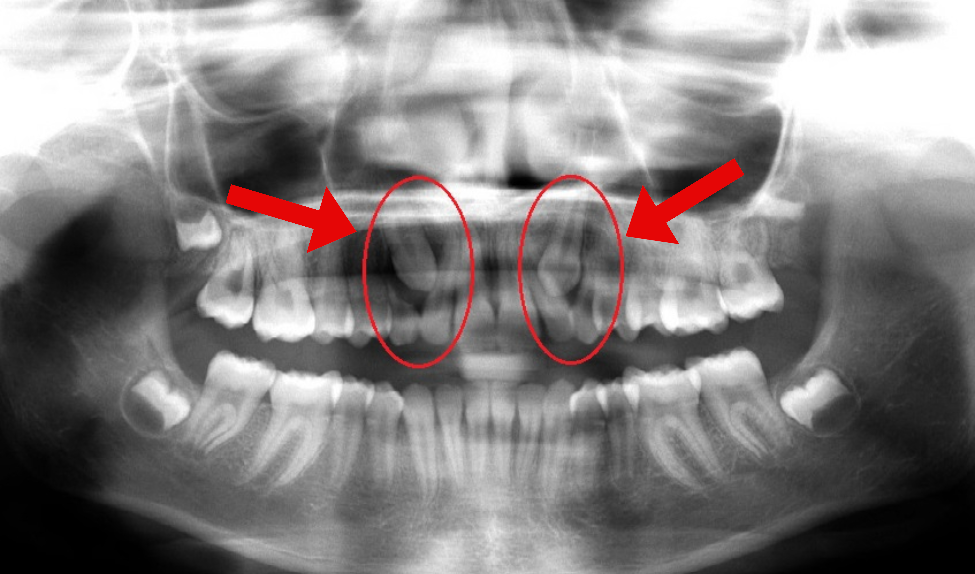

Caso 1

En la primera foto, sus colmillos permanentes superiores estaban creciendo en la dirección equivocada. Después de extraer los colmillos de leche superiores, los dientes permanentes se corrigieron por sí solos y comenzaron a erupcionar normalmente, como se muestra en la segunda foto.

Esta intervención temprana evitó que la paciente desarrollara caninos impactados. Esto significa que su tiempo de tratamiento fue al menos 12 meses más corto, evitó la cirugía en ambos colmillos superiores y hizo que todo el proceso de tratamiento fuera mucho más cómodo.